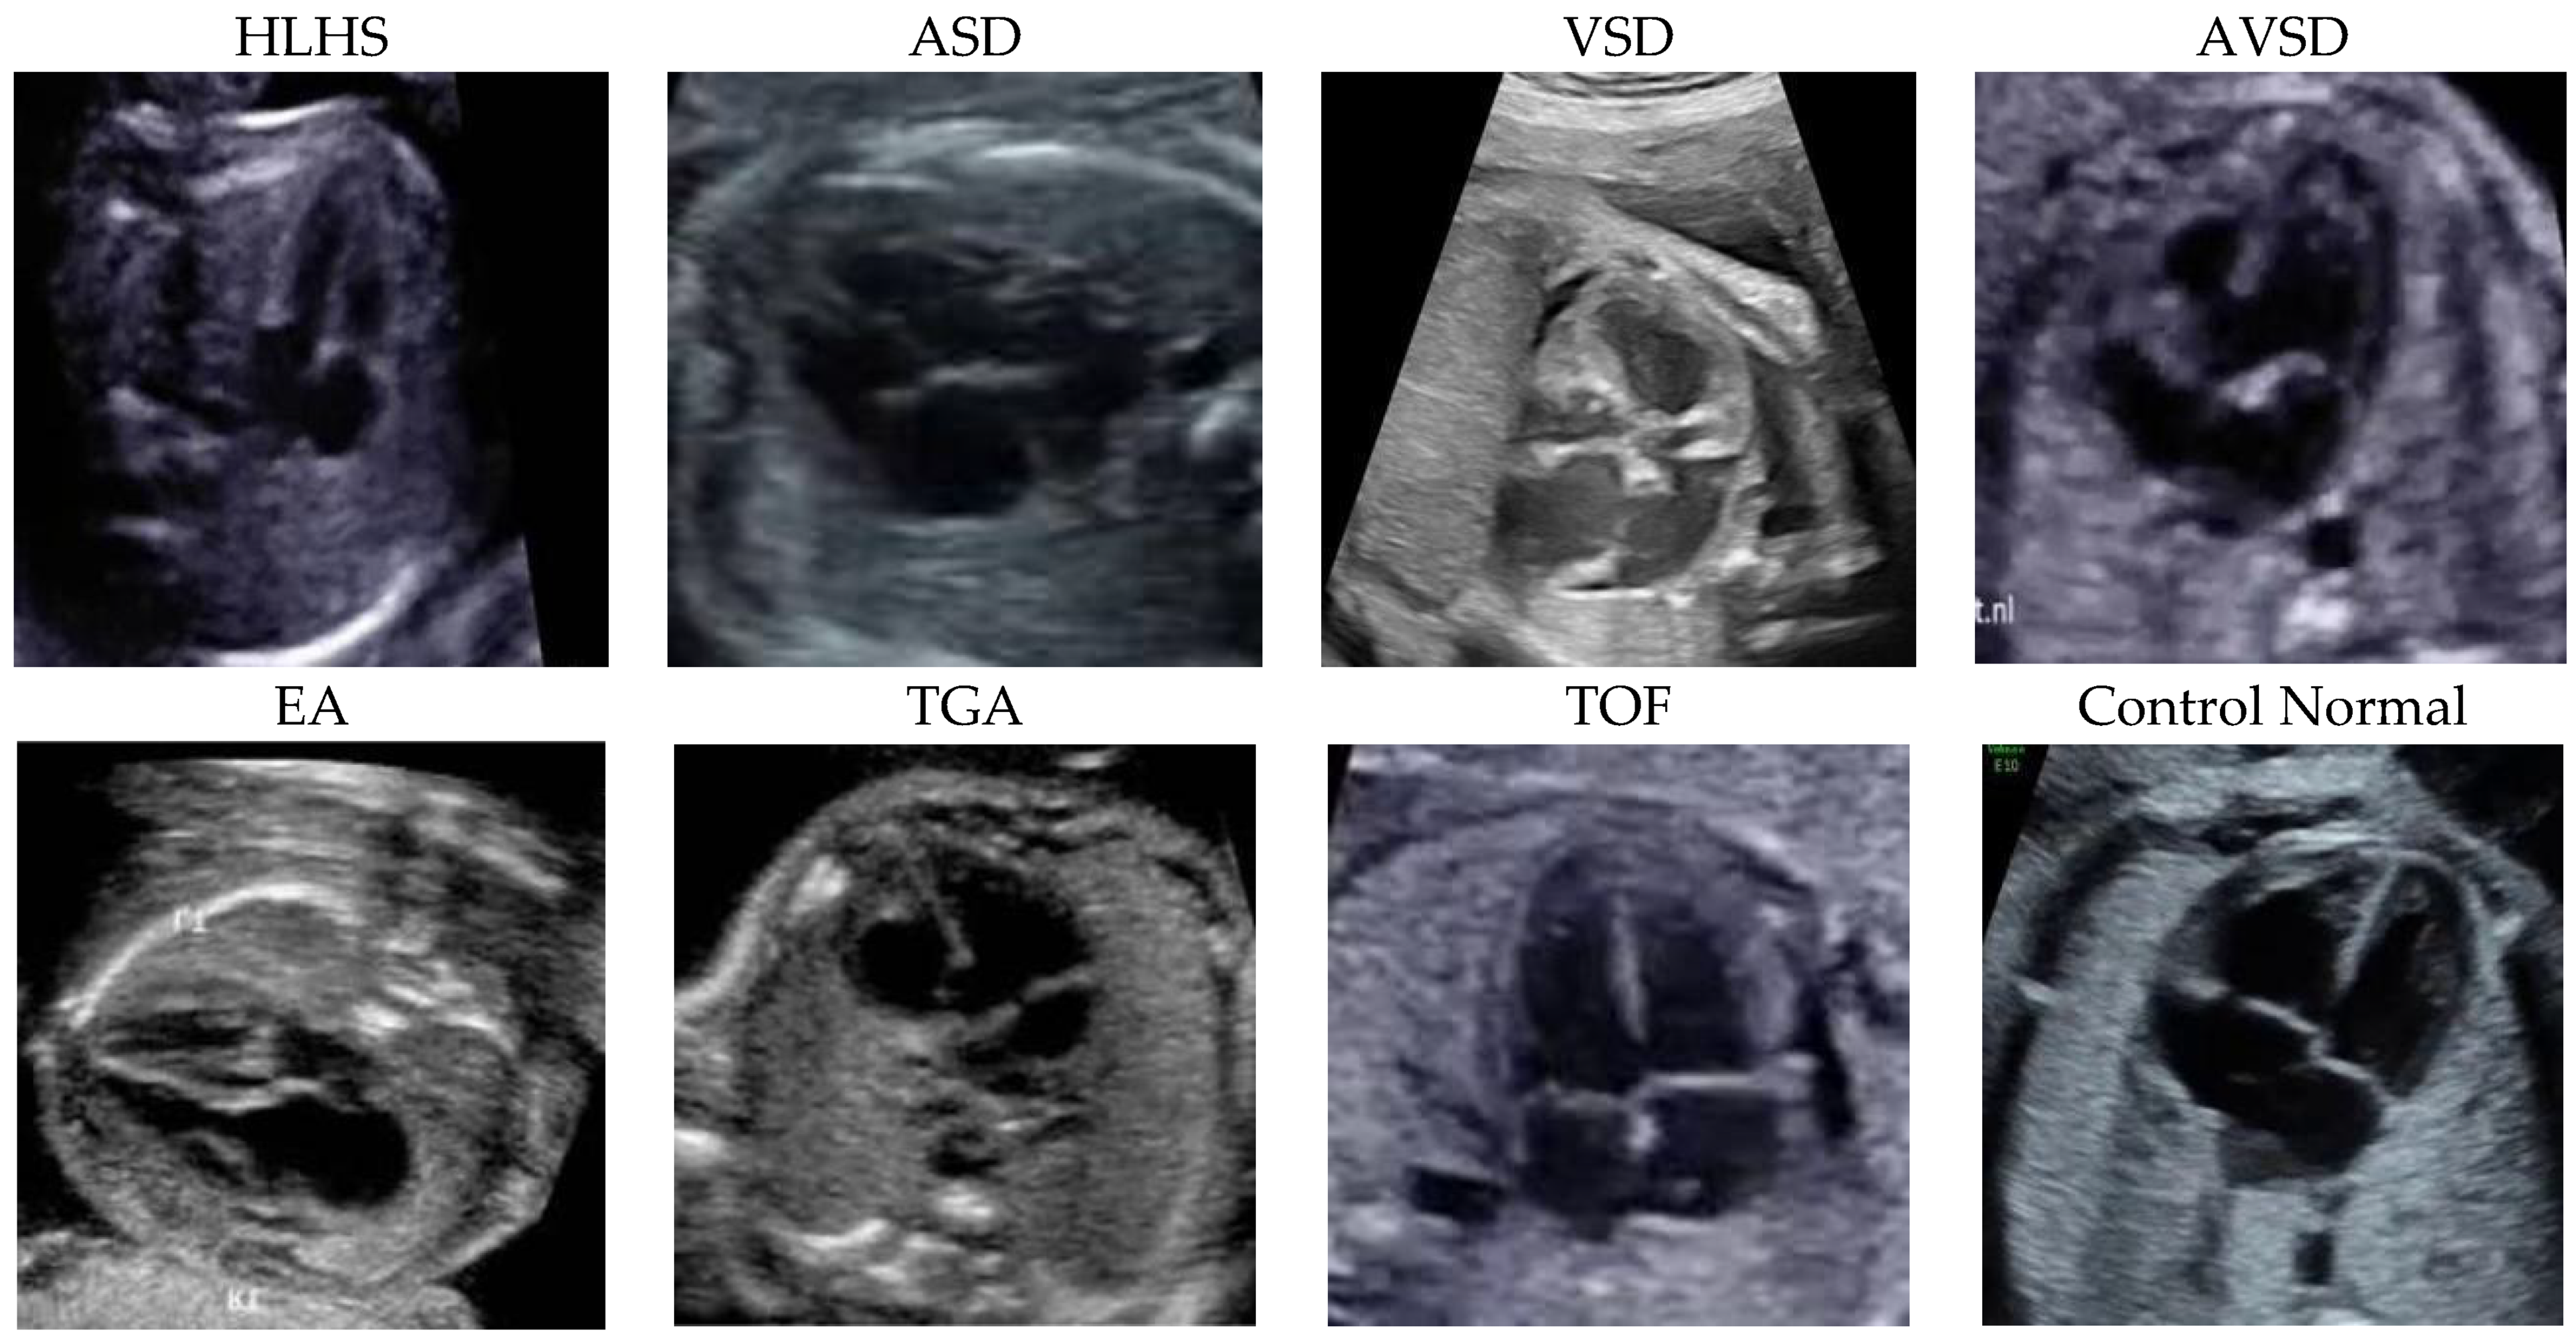

Figure 1 depicts the sample of seven diseases, including ASD, VSD, AVSD, EA, TOF, TGA, HLHS, and control echocardiograms from fetal USG. Each patient’s data were collected as raw ultrasound digital imaging and communications in medicine (DICOM) videos. These fetal USG videos are unannotated with precise standard planes, typically used for diagnosis. However, the size of each frame is converted from 640 × 480 pixels to 300 × 300 pixels. Table 1 summarizes the distribution of the frames.

Figure 1.

The samples were fetal heart images with seven diseases and a normal control. The entire patient was collected from Mohammad Hoesin General Hospital, Palembang. Indonesia.